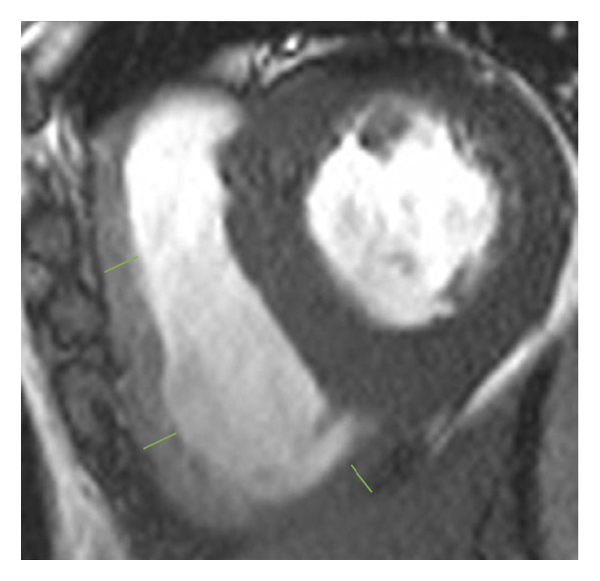

2.3. 이미징 분석모든 이미지 분석은 시중에서 판매되는 소프트웨어(cvi42, Circle Cardiovasic Imaging, Inc. Calgary, Canada)를 사용하여 수행되었습니다. 심장 기능을 측정하기 위해 심장내막 및 심외막 추적을 확장기 말기 및 수축기 말기의 직렬 단축 슬라이스에서 수동으로 수행했습니다. LV/RV 확장기말 용량(EDV), 수축기말 용량(ESV) 및 LV/RV 박출률을 포함한 전체 LV/RV 수축기 기능이 계산되었습니다. LV 및 RV 심근 스트레인 분석은 장축 4챔버 및 단축 슬라이스를 조직 추적 모듈에 로드하여 수행되었습니다(그림 1 (a) 및 1 (b)). RVT는 중실의 3회 측정하였고, 평균 두께를 계산하였다(도 1 (c) 및 1 (d)). GRPS(글로벌 라디칼 피크 변형), GLPS(글로벌 세로 피크 변형) 및 GCPS(글로벌 원주 피크 얼룩)를 포함하여 전역 특징 추적 매개변수가 자동으로 획득되었습니다. 최고 수축기 변형률(PSSR, 이완기부터 다음 수축기까지의 모든 단계에 대한 절대값의 최대 변형률)과 최고 확장기 변형률(PDSR, 수축기부터 다음 수축기까지 모든 단계에 대한 절대값의 최대 변형률)은 다음과 같습니다. 또한 분석했다. 양수 기호와 음수 기호는 서로 다른 동작 방향을 나타냅니다. 앞서 기술한 바와 같이[ 16 ], 정상적인 RVT 값은 7mm 이하로 정의되었다. 기준에 따라 CA 및 HCM 환자를 RV 비대(RVT >7 mm) 또는 RV 비대(RVT ≥7 mm) 환자에 따라 하위 그룹으로 나누었습니다.